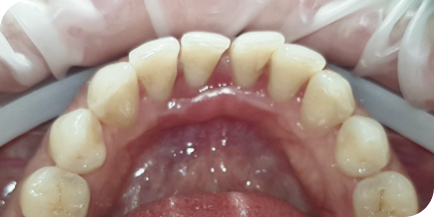

Случай из практики.

Наращивание десны

Часто наши пациенты спрашивают, через какое время после наращивания десна снова опустится вниз. С уверенностью могу сказать, что при соблюдении всех рекомендаций зубы, которые были уже на грани удаления, будут служить пациенту всю жизнь!

Пациентку (Екатерина, 55 лет) в нашу клинику отправили из другой клиники наши коллеги. Цель — вылечить и нарастить десну перед протезированием зубов.

Это был непростой клинический случай с наращиванием десны

в эстетически значимой зоне.

На фотографиях исходное состояние, состояние спустя год после наращивания и 5 лет после наращивания. Результат стабилен.

Десна после наращивания никогда не опустится, если пациент соблюдает все рекомендации врача: приходить на регулярные профилактические осмотры.